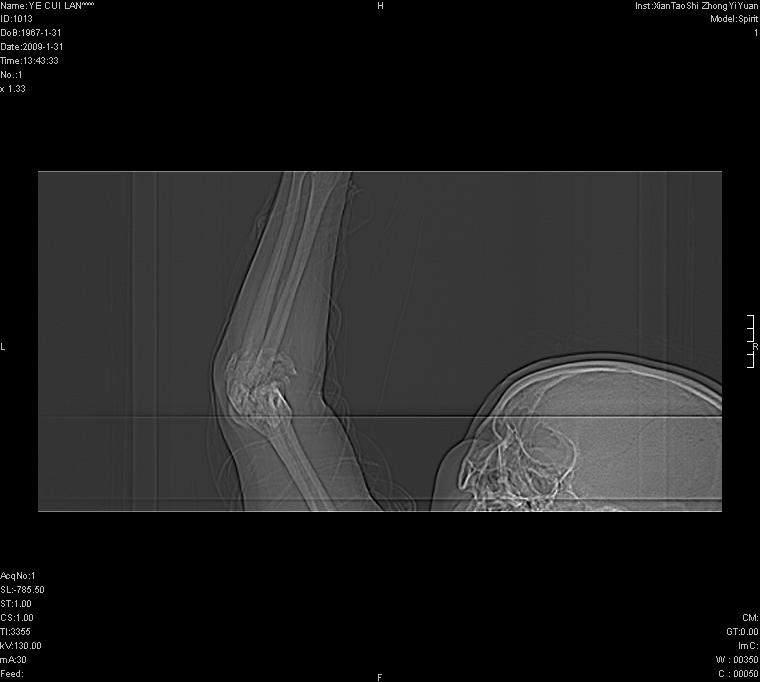

以下是引用王明发在2009-2-9 11:53:00的发言:[br]支持夏科氏关节,必要时行脊髓mri检查 [br]夏科氏关节是指由于某些神经系统疾病引起的关节病变,也被称为神经性关节炎。常见病因有脊髓痨、脊髓空洞症等。原发的神经病变可以造成关节深部感觉障碍,对于关节的震荡、磨损、挤压、劳倦不能察觉因而也不能自主地保护和避免,而神经营养障碍又可使修复能力低下,使病人在无感觉状态下造成了关节软骨的磨损和破坏,关节囊和韧带松弛无力,易形成关节脱位和连枷关节。关节面的破坏和骨赘的脱落变成关节内游离体。关节外形饱满肿胀,内有出血和渗出。这种病早期并无疼痛,不易被病人重视,仅表现为关节肿胀、无力、活动过度、动摇不稳。关节肿胀、无痛、活动范围超常是本病的重要特征。x光片可见有关节骨端广泛破坏、硬化或呈奇异形态,骨赘形成,关节间隙不规则或增宽,周围软组织钙化、关节内游离体、骨碎片等。结合x光片及临床症状,病人又有神经系统原发病症,即可确诊

以下是引用hhcckk在2009-2-9 14:31:00的发言:[br]夏科关节的六大表现[br]1.关节软组织肿胀。[br]2.关节的脱位与半脱位。[br]3.关节内的游离体。[br]4.关节面硬化,新骨形成。[br]5.骨质萎缩与破坏。[br]6.关节结构的紊乱。[br]加上患者无明显疼痛,诊断的把握性比较大